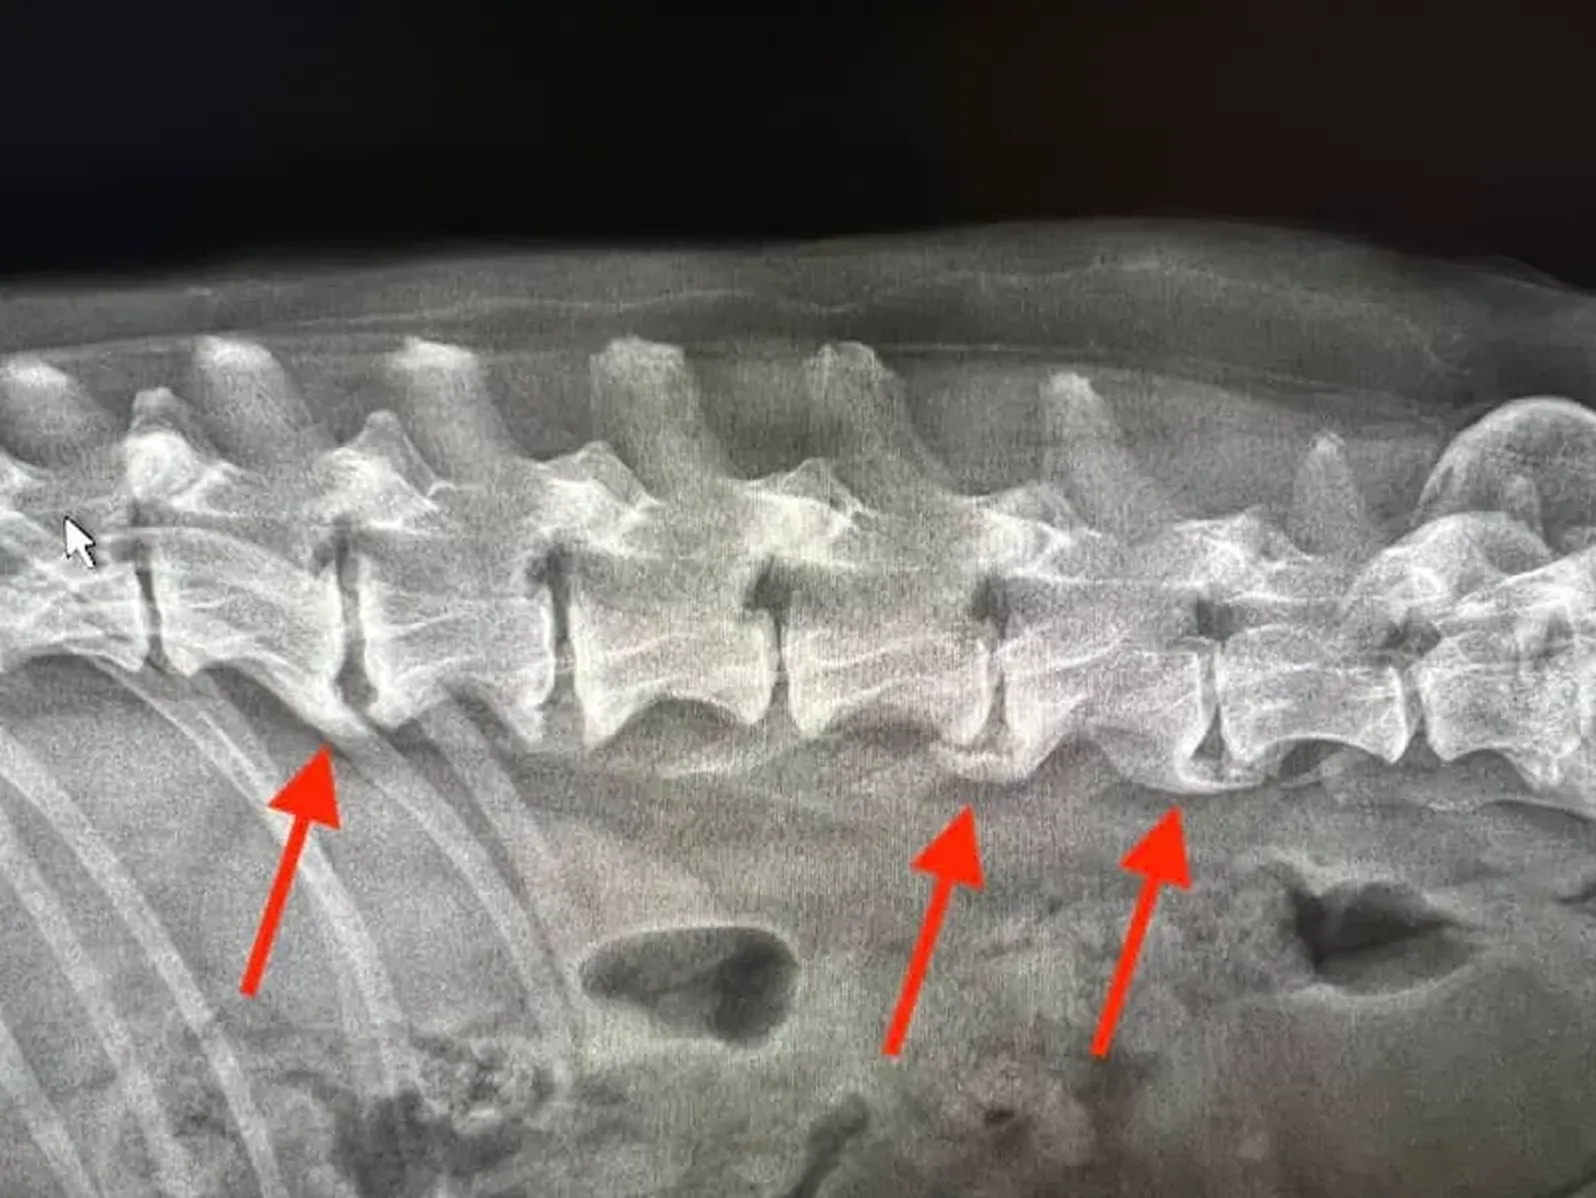

Degenerative myelopathy is nerve death.

The myelin coating around your dog's spinal cord nerves—the insulation that lets signals travel from brain to legs—starts breaking down.

It's like rust spreading through electrical wiring.

First, the signals slow down...

Then they misfire.

Then they stop completely.

And every single day that passes? More nerves die.

Once they're gone, they don't come back.

By the time your vet diagnoses it, 60-70% of the spinal cord nerves may already be damaged.